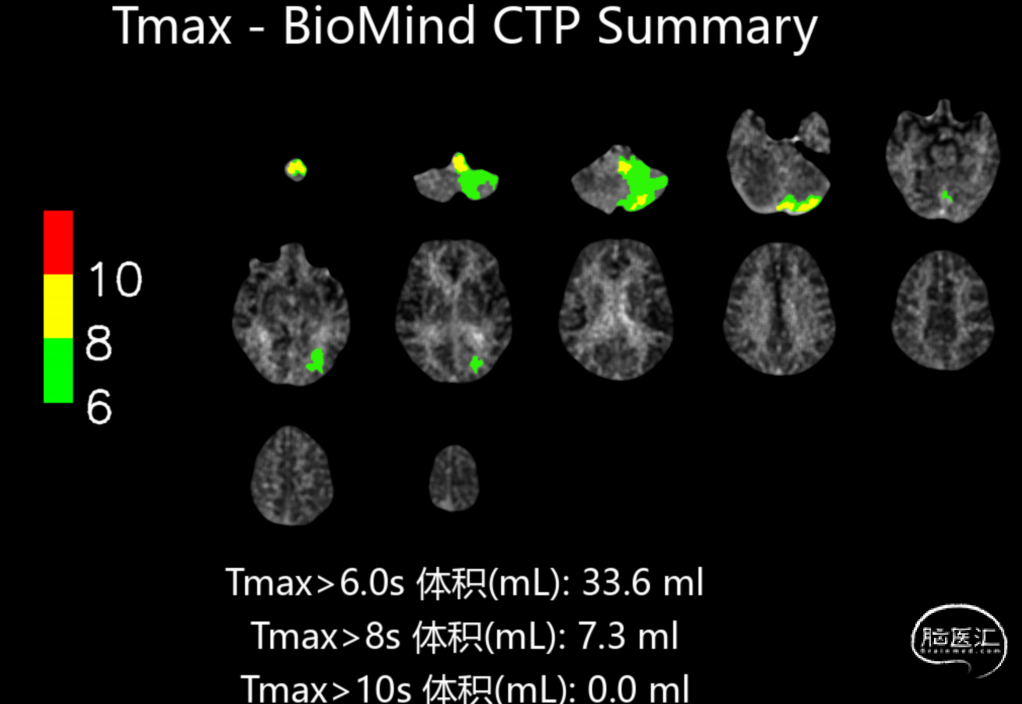

➢2024.07.10 CTP提示:

小脑半球低灌注